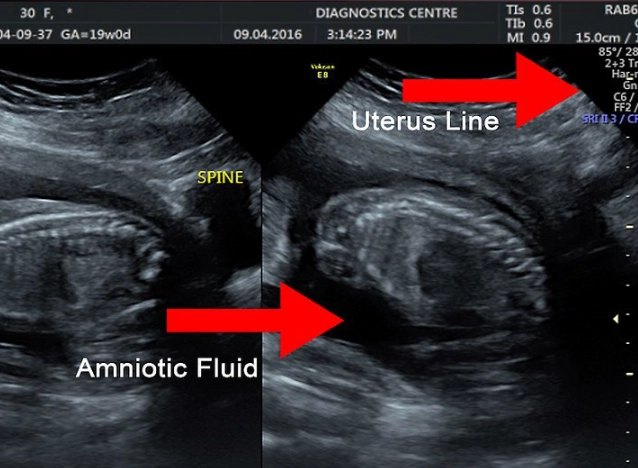

Placenta, Amniotic Fluid, and Cervix

- Amniotic Fluid Index (AFI) or Deepest Pocket (DP): Measures the amount of fluid around the baby. Too much (polyhydramnios) or too little (oligohydramnios) can be associated with certain conditions.